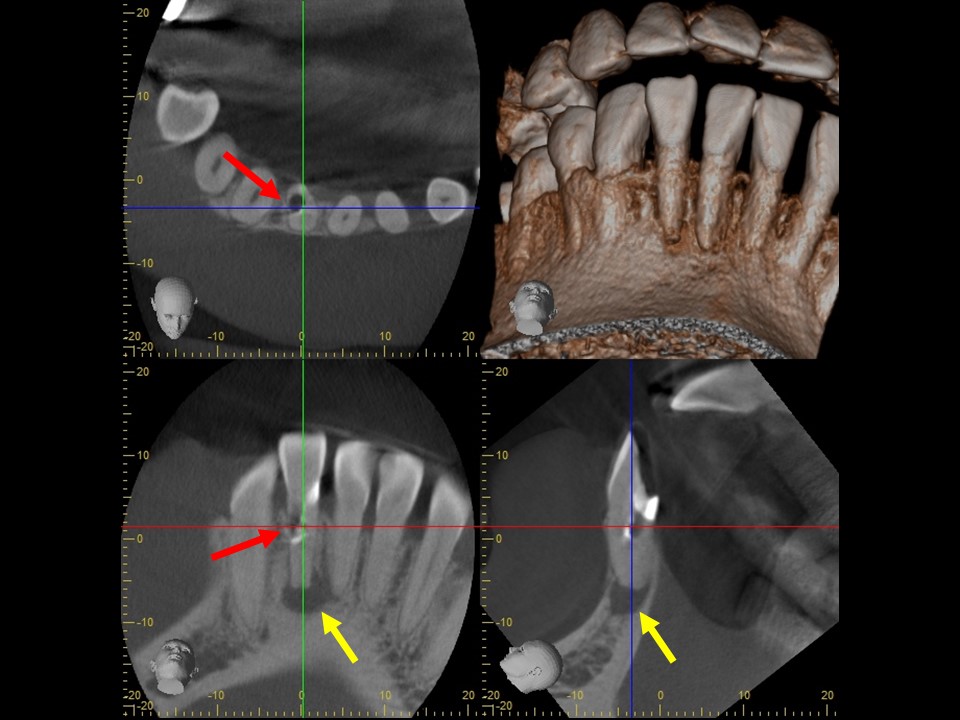

診断と治療計画の立案

当該の左下7番の奥歯はクラウンで被せてありましたが、頬側に歯茎の腫れ(フィステル、サイナストラクト)を認めました。レントゲンおよびCTによる診査を行ったところ、すでに根管治療が施してあるものの根管充填が不十分で、根尖病変を生じていました(下写真)。また、歯根の先端部分にはファイルと思われる器具の破折片を認めました(矢印)。根管内部へのバクテリアの感染による慢性化膿性根尖性歯周炎と診断し、再根管治療をおこなうことにしました。

治療前レントゲン | 治療前CT |

治療前レントゲン |

---|

治療前CT |

治療前のレントゲンおよびCT画像です。当該歯はすでに根管治療が施してあり、根尖部には根尖病変によるX線透過像を認めます。

また、根尖部にはファイルと思われる器具の残存を認めます(矢印)。

ガッタパーチャを除去したところです。CT画像にて根尖部に破折しているファイルが残っているのが確認できます(矢印)。